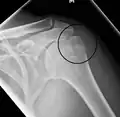

Proximal

Proximal humerus fractures most often occur among elderly people with osteoporosis who fall on an outstretched arm.[9] Less frequently, proximal fractures occur from motor vehicle accidents, gunshots, and violent muscle contractions from an electric shock or seizure.[10][5] Other risk factors for proximal fractures include having a low bone mineral density, having impaired vision and balance, and tobacco smoking.[11] A stress fracture of the proximal and shaft regions can occur after an excessive amount of throwing, such as pitching in baseball.[6]

Definitive diagnosis of humerus fractures is typically made through radiographic imaging. For proximal fractures, X-rays can be taken from a scapular anteroposterior (AP) view, which takes an image of the front of the shoulder region from an angle, a scapular Y view, which takes an image of the back of the shoulder region from an angle, and an axillar lateral view, which has the patient lie on his or her back, lift the bottom half of the arm up to the side, and have an image taken of the axilla region underneath the shoulder.[9] Fractures of the humerus shaft are usually correctly identified with radiographic images taken from the AP and lateral viewpoints.[12] Damage to the radial nerve from a shaft fracture can be identified by an inability to bend the hand backwards or by decreased sensation in the back of the hand.[5] Images of the distal region are often of poor quality due to the patient being unable to extend the elbow because of pain. If a severe distal fracture is suspected, then a computed tomography (CT) scan can provide greater detail of the fracture. Nondisplaced distal fractures may not be directly visible; they may only be visible due to fat being displaced because of internal bleeding in the elbow.[7]